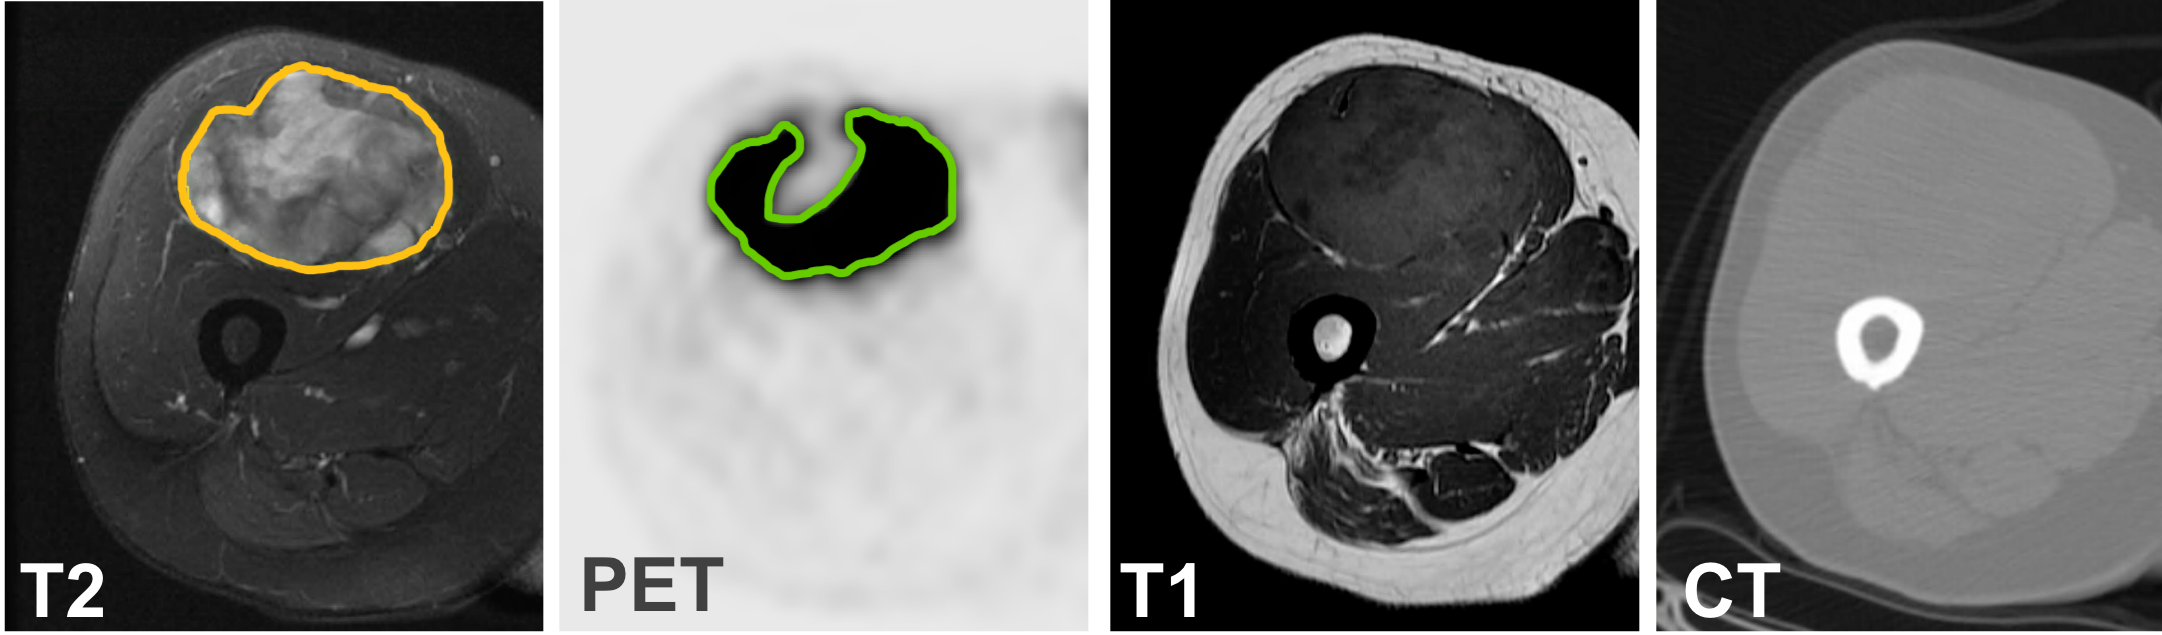

Refer to caption

Figure 1: Depending on the modality and the clinical intent, the segmentation for soft tissue sarcomas on the MRI T2 scan (yellow contour) and the PET scan (green contour) may look different. Figure best viewed in color.

Soft tissue sarcomas are malignant tumors that originate from various tissues, including muscular tissue, connective tissue, and nervous tissue. They predominantly occur in the extremities. Due to their large size, soft tissue sarcomas tend to form necrotic tumor areas. In MRI scans, necrosis is considered part of the tumor, but it is not visible on the PET scan as the necrosis is no longer metabolically active. Fig. 1 demonstrates the challenge of multimodal segmentation for soft tissue sarcomas on PET and MRI scans.